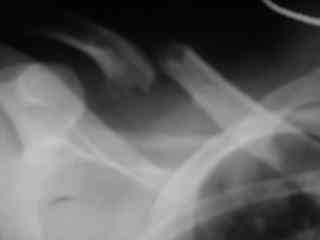

C> Postupil ko mne bolnoi s perelomom obeih kluchits, neznachitelny

C> pneumotorakx sleva.

Накостный остосинтез обех ключиц в одну сессию рекон.пластиной в условиях интубационного наркоза с положительным ПДКВ (+ 5-7 мм вод. ст.) и интраоперационным контролем степени пневмоторакса. Возможно, дренирование плевральной полости слева, по результату рентгенконтроля, по Бюлау.

Справа перелом практически поперечный, можно попробовать интрамедуллярно стержнем. Личного опыта правда не имею, у нас стандартом при оперативном лечении переломов ключицы является тот же остеосинтез пластиной. Но в литературе описана методика даже закрытого остеосинтеза - так, в порядке обсуждения.